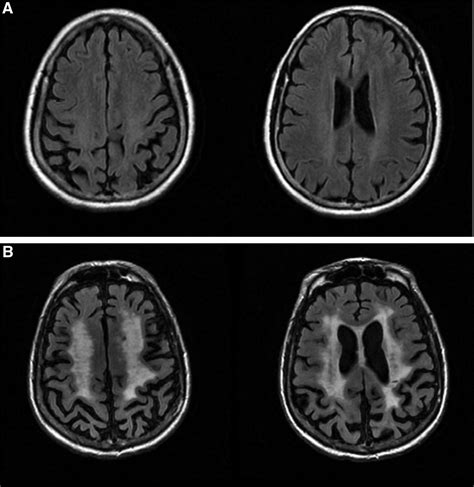

Diagnosis is usually confirmed via an MRI of the brain, which provides a detailed look at the white matter. Radiologists look for specific patterns, such as leukoaraiosis or hyperintensities, which appear as "bright spots" on the scans. These spots indicate areas where the brain tissue has been affected by chronic ischemia.

White Matter Hyperintensities (WMH) Indicates long-term vascular stress and potential cognitive slowing.

Lacunar Infarcts Small, fluid-filled cavities resulting from past tiny strokes.

Microbleeds Tiny hemorrhages indicating fragile vessel walls.

Brain Atrophy Loss of overall brain volume, often associated with advanced disease.